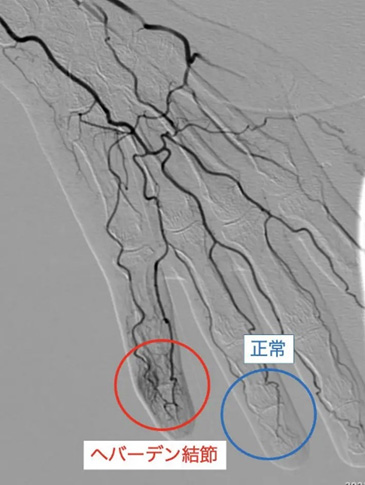

ヘバーデン結節に対する治療効果